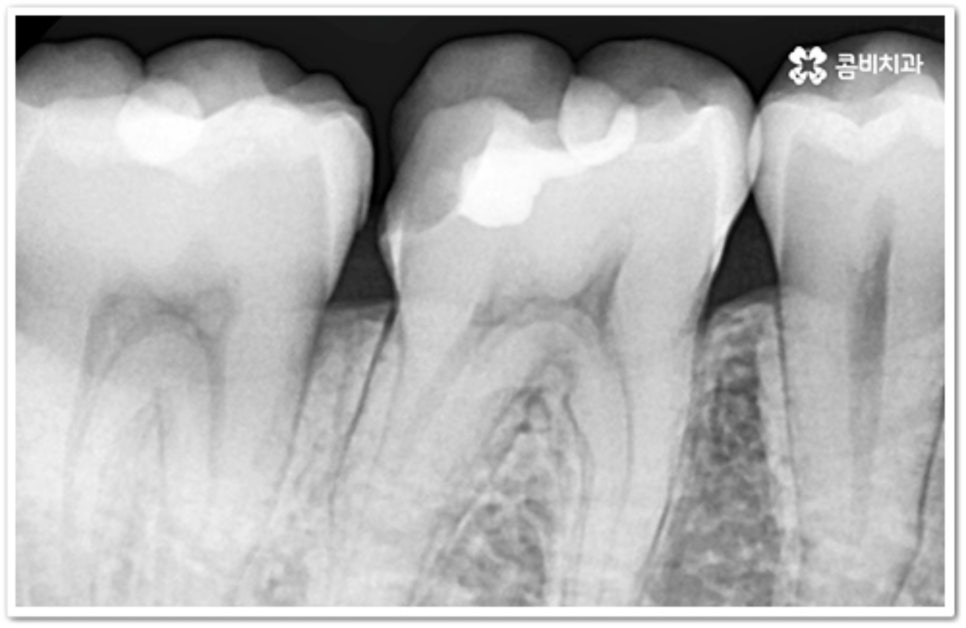

충치는 시간을 두고 단계적으로 진행하는 구강 질환이기 때문에 초기에 발견하여 빠르게 대처해 주는 것이 구강 건강을 위해 보다 바람직한 방법이라 할 수 있습니다. 흔히 우리가 충치라고 부르는 치아 우식증은 발생 위치에 따라 두 가지 종류로 나눌 수 있는데요. 보통 위아래 치아가 마주보는 교합면에 생기는 충치는 육안으로 발견할 가능성이 높고 접근이 용이하기 때문에 치료가 쉬운 편이지만, 치아 사이에 생기는 인접면 충치 는 맞닿은 치아로 인해 노출이 잘 되지 않기 때문에 발견도 어렵고 상황에 따라 치료할 때 기구를 손상 부위까지 닿게 하기 위해 치아 삭제가 많이 이루어져야 하는 경우도 있는 등 좀 더 까다로울 수 있어요.

치아의 구조를 살펴보면 안쪽의 무른 조직을 감싸고 있는 단단한 바깥쪽 법랑질은 교합면에서 가장 두껍고 잇몸쪽으로 갈수록 얇아지기 때문에 인접면에 생긴 충치의 경우 조금만 진행 되어도 손상이 내부 신경까지 보다 빠르게 번질 수 있어요. 신경치료를 받은 치아는 정상 치아에 비해 외부 충격에 취약해지므로 가능한 한 그 단계에 이르기 전에 적절한 치료를 받으실 필요가 있는데요.

하지만 앞니가 아닌 안쪽 어금니의 인접면 충치 라면 증상이 없고 발견이 쉽지 않기 때문에 초기에 발견하고 치료를 하는 것이 힘들 수 있어요. 그렇기 때문에 평상시에 꾸준히 검진을 받고 치실을 사용하여 칫솔질을 꼼꼼하게 해 주는 것이 더욱 중요한 거예요.

인접면에 충치가 생겼을 때 치료 과정은 손상 정도에 따라 달라질 수 있는데 만약 아주 경미하다면 바로 레진으로 이를 수복할 수 있겠지만 치아 경계면이 무너졌다면 직접적인 레진 수복으로는 생리학적 형태를 재현하기 까다롭기 때문에 본을 떠서 외부에서 금이나 세라믹 보철물을 만들어 끼워넣는 간접적인 방법을 통해 도움을 받을 수 있어요. 환자분들의 상황에 따라 치아 일부만 수복해야 할 때는 인레이 치료를 하고 손상이 크면 신경치료를 한 후 필요시 내부에 기둥을 세우고 치아 전체를 다듬어 씌우는 크라운 치료를 이용하게 될 거예요.